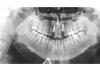

Заринка Опубликовано 12 октября, 2013 Поделиться Опубликовано 12 октября, 2013 (изменено) Мне 29 лет и у меня было 2 молочных боковых резца на верхней челюсти. Сохраняла как могла, но увы... один сломался. Проконсультировавшись с доктором, было принято решение сделать синус-лифтинг, т.к. кость атрофировалась и установить 2 импланта. В мае была проведена операция. По прошествии 4-х месяцев был сделан снимок, который показал, что на левой стороне кость сформировалась не так как нужно, но возможность установки есть, просто имплант будет поставлен чуть выше второго (со слов доктора) и 24.09.2013г. мне установили импланты. С этой стороны уже сейчас видно как ушла десна, смотрится очень не красиво. Можно ли это как то исправить? и на каком этапе?Заранее спасибо. Изменено 12 октября, 2013 пользователем Заринка Ссылка на комментарий

Bier Опубликовано 18 октября, 2013 Поделиться Опубликовано 18 октября, 2013 скорее всего там инфицирована поверхность имплантата. Сделайте КТ, судя по всему он частично не в кости. 1 Ссылка на комментарий

Заринка Опубликовано 22 октября, 2013 Автор Поделиться Опубликовано 22 октября, 2013 от подобных промываний и антибиотиков толку нет, удаляйте имплантат. Видимо Вы правы, только закончился 3 курс антибиотиков и промывание, на этом же месте сегодня снова образовалась шишка (свищ)! За чей счет в моем случае будет переустановка имплантов? Спасибо. Ссылка на комментарий